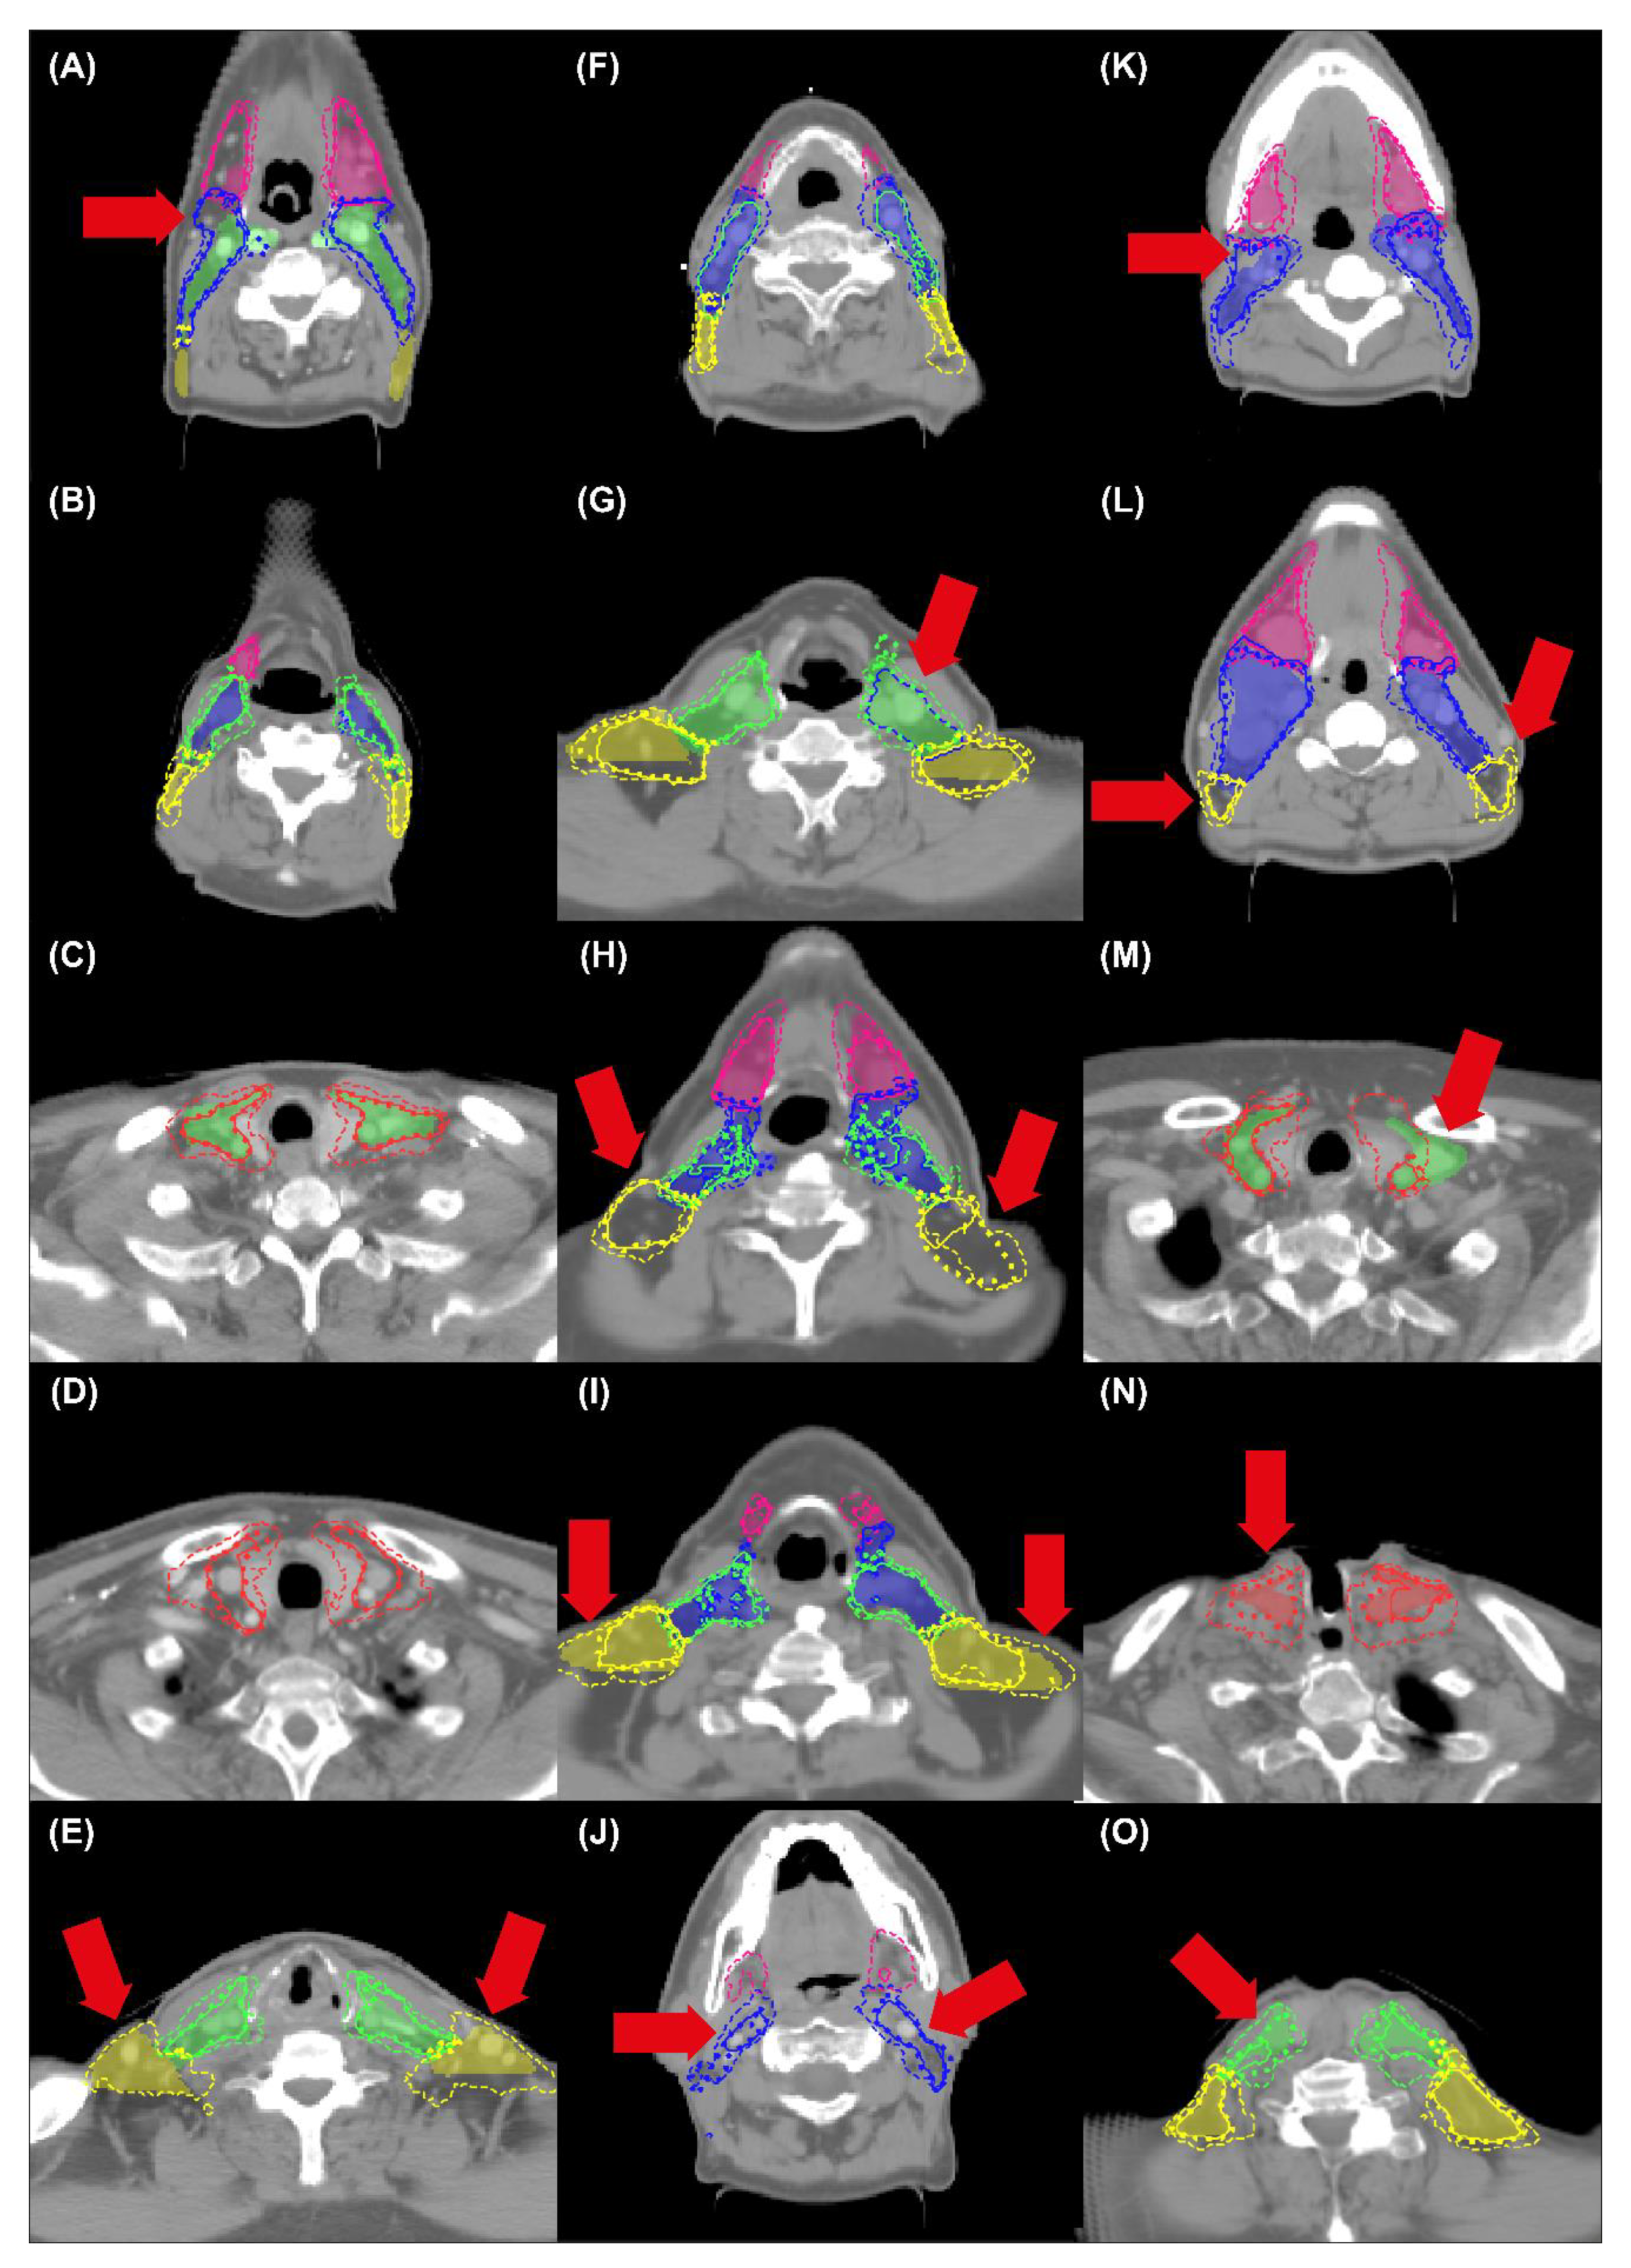

3. Results